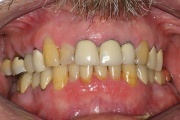

Kõige tavalisem kaebus sülje hüpofunktsiooni korral on püsiv, terve päev kestev suukuivus. Selline seisund nõuab sagedat joomist. Inimesed ärkavad tihti keset öö ja on sunnitud võtma klaasi vett endaga voodisse. Tuleb eristada aga neid, kes ärkavad põhiliselt hommikul, sest suukuivuse Loe edasi »